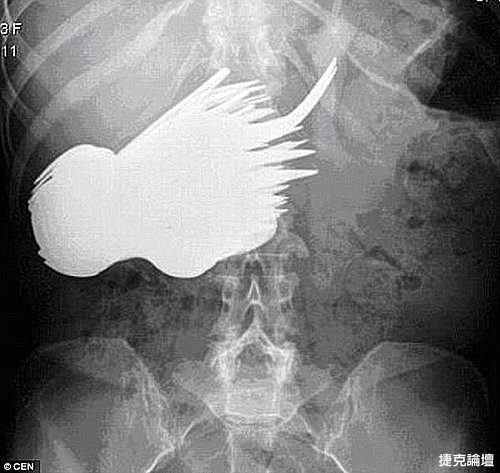

X光片顯示,瑪格麗特的胃�有很多餐具。

30年前,荷蘭女子瑪格麗特·達阿爾瑪因為胃痛難忍,到鹿特丹一家醫院檢查。診斷結果令人瞠目結舌:瑪格麗特的胃�竟然有78把銀制勺子和叉子。這段奇聞軼事直到最近才被德國一家醫學雜誌曝光。

根據德國醫學雜誌《精神病在線雜誌》的披露,30年前,年僅22歲的瑪格麗特被查出胃�竟然有78把餐具。醫生立即為她實施了手術,將胃中的勺子和叉子一個接一個地取了出來。在場的醫生和護士十分不解,她為什麼會吞餐具。